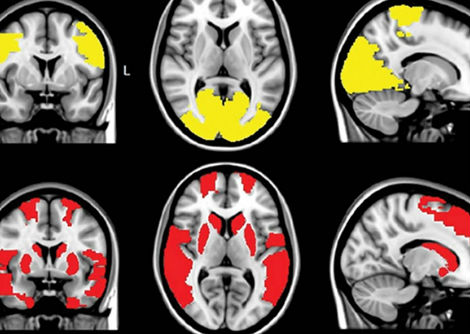

يُستخدم العمر البيولوجي لتقدير كفاءة وظائف الجسم مقارنةً بسنوات عمر الشخص الفعلية. تعتمد هذه القياسات على مثيلة الحمض النووي، وهي عبارة عن علامات كيميائية صغيرة تعمل كعلامات تنظيمية على الحمض النووي وتتغير تدريجيًا مع تقدمنا في العمر.

لتقدير العمر البيولوجي، استخدم الباحثون نوعين من التقييمات. ركز أحدهما على التغيرات الكيميائية في الحمض النووي التي تدل على سرعة الشيخوخة، بينما قاس الثاني طول التيلوميرات. التيلوميرات هي تراكيب واقية في نهايات الكروموسومات، وعادةً ما يرتبط قصرها بالشيخوخة والمشاكل الصحية المرتبطة بها.